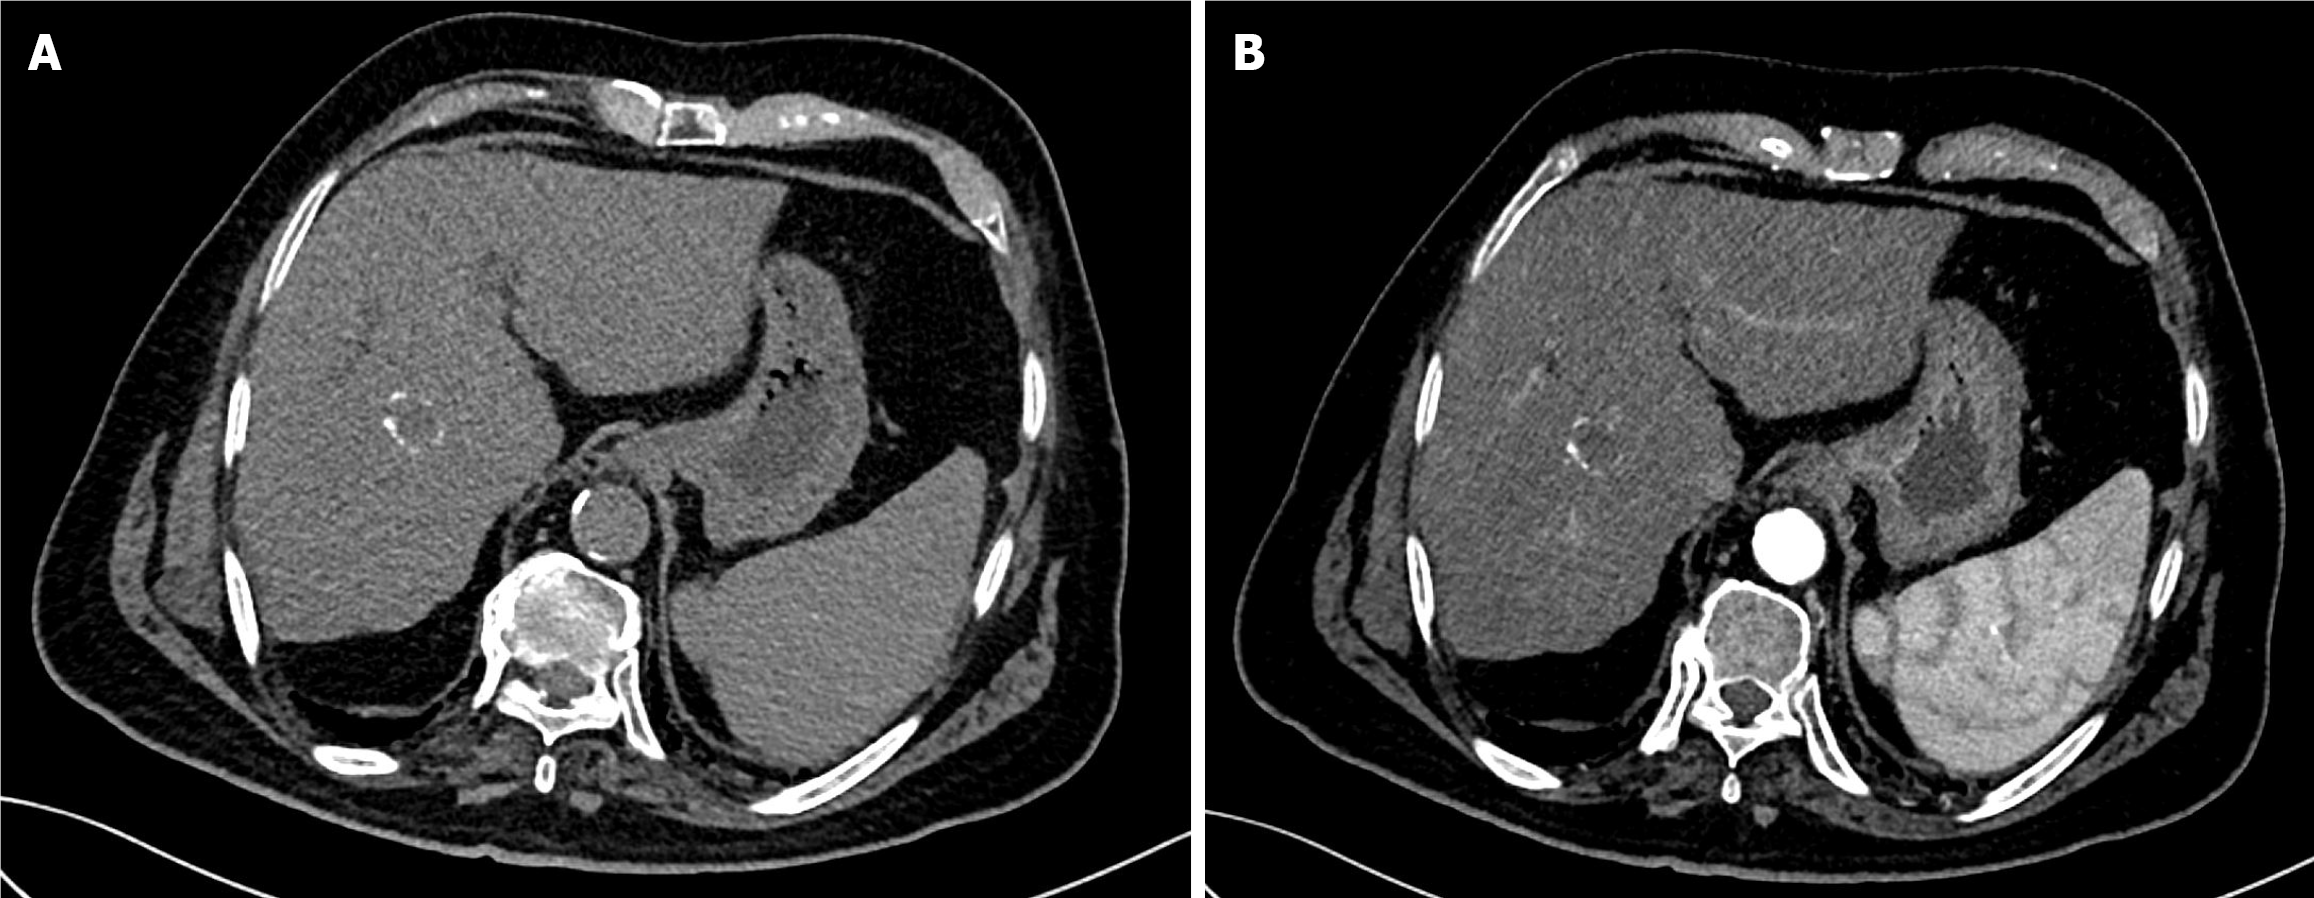

Figure 5 Six-week follow-up computed tomography of the abdomen after the first drug-eluting bead transarterial chemoembolization in Case 1.

A: Arterial phase computed tomography (CT) showed a residual hypervascular nodule at the periphery of the non-enhancing treated mass, indicating partial response; B: Delayed phase CT confirmed washout of the residual soft tissue nodule.